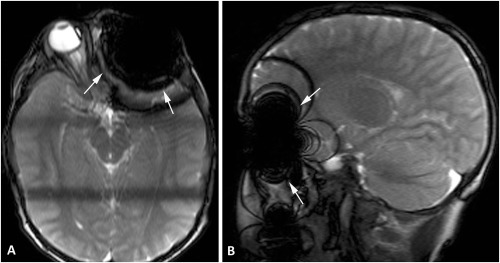

No je tam riziko ak to nevyde dovtedy. MR na alobal vplyv mat nebude ziaden ale na obrazku sa okolo toho alobalu urobi neviditelna cierna diera takze ak tam bude zrovna nejaky problem tak ho neuvidia.

Tutok mal borec nepriznanu 3,5mm kovovu triesku vo viecku o ktorej nevedel lebo ho netrapila. MR je potom okolo toho slepe a nic nevidi

@teki1 nie , je to len vypadok obrazu. Nic sa fyzicky nedialo , nikto netusil ze tam nieco ja , az ked sa zacal tvorit obraz tak to prerusili a poslali ho na ct

@teki1 tu je obrazok z ct potom